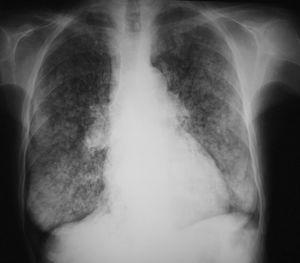

La paciente ingresó en varias ocasiones por descompensación respiratoria secundaria a infección bronquial. Clínicamente presentaba disnea a esfuerzos moderados. En la actualidad presentaba nefropatía crónica del trasplante, por lo que se planteó un nuevo trasplante y se consultó a neumología para valorar la enfermedad pulmonar y el riesgo quirúrgico secundario. La radiografía de tórax mostraba un patrón nodulillar difuso bilateral, sin pérdida de volumen pulmonar (fig. 1). La exploración funcional respiratoria puso de manifiesto una limitación moderada al flujo aéreo e intensa reducción de la transferencia al CO. La capacidad vital forzada (FVC) era de 2,20 l (un 74% del valor de referencia [VR]), el volumen espiratorio forzado en el primer segundo (FEV1) de 1,37 l (63% del VR), el cociente FEV1/FVC del 62%, la capacidad residual funcional del 88% del VR, el volumen residual del 110% del VR, la capacidad pulmonar total del 91% del VR, la capacidad de difusión de CO (DLCO) del 41% del VR y DLCO/volumen alveolar del 46% del VR. Los valores de la gasometría arterial en reposo fueron: presión arterial de oxígeno (PaO2) de 82 mmHg, presión arterial de anhídrido carbónico (PaCO2) de 45 mmHg, pH de 7,41 y bicarbonato de 27 mEq/l. La TAC torácica demostró múltiples calcificaciones distribuidas en partes blandas de forma difusa, principalmente localizadas en el tejido subcutáneo; adenopatías calcificadas en la región traqueobronquial izquierda; calcificaciones aórticas y de anillo valvular mitral, y múltiples calcificaciones vasculares arteriales. En el parénquima pulmonar se evidenciaron múltiples infiltrados en vidrio deslustrado y de distribución centrolobulillar, que afectaban difusamente y de forma extensa ambos campos pulmonares (fig. 2). Todos estos hallazgos eran muy indicativos de calcificaciones metastásicas en relación con el hiperparatiroidismo terciario, secundario a la insuficiencia renal crónica.

Fig. 1. Radiografía de tórax de una paciente con calcificaciones pulmonares asociadas a insuficiencia renal crónica. Se observa un patrón nodulillar difuso bilateral.